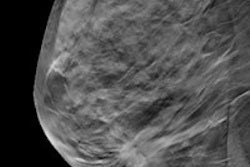

In one study, EM Imaging will supply EMI-137, a clinical-grade investigational molecular optical imaging agent, to two investigational sites to perform clinical efficacy studies for pancreatic and lung cancers. The Edinburgh Royal Infirmary will evaluate suspected lung cancer patients, while Groningen Medical Center in the Netherlands will study EMI-137 in early-stage pancreatic cancer. Both centers will image EMI-137 in real-time at the cellular level using endomicroscopy with Cellvizio.

In a second study, EM Imaging will provide EMI-200, a neutrophil-targeting optical molecular imaging agent developed for topical administration in the lung. The presence of neutrophils in the lung is correlated with an inflammatory response, and as such is clinically useful in the acute-care setting to improve diagnosis of critically ill patients, the firms said. Exams will be performed at the Cleveland Clinic in Ohio in acute-care patients, and the Cellvizio platform will be used to image neutrophil activity in real-time at the cellular level.